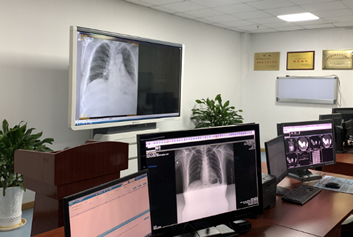

远程影像诊断/医联体软件迈德卫云影像-跨越千里的生命回响:一场远程会诊,为重症老人重燃希望“要是再晚一步,我父亲可能就真的没救了!”回想上个月的经历,家住偏远县城的张先生仍心有余悸。而让他全家从绝望边缘走出来的,不是奔波千里的转诊,而是一场跨越2000多公里的远程会诊。在医疗资源分布不均的当下,这样的故事,正在无数个普通家庭中悄然上演。跟着远程影像...